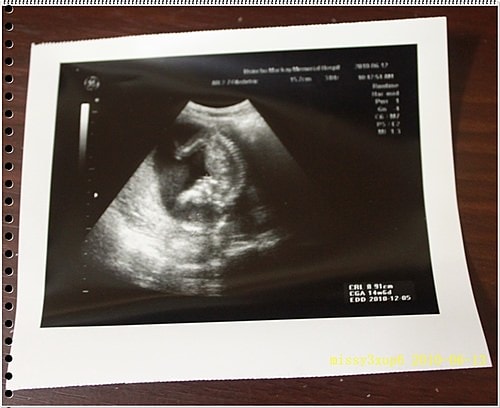

很好!你這小子= =,你娘36W產檢日誌都還沒打,你就這樣趕著來了,說好得38w呢? 36W紫琳去做了乙鍊,醫生說胎頭很低,但子宮頸還好,可能再一兩次產檢就會生…

由於最近心情不太穩定,身體也有點不好,這篇一直拖著,但這篇應該是我第一次產檢完,會馬上想到紀錄重點的吧?! 相較於第一胎在診所產檢,大家都說大醫院很趕很忙很快,診所仔細方便…

這次去馬偕其實是21W了,我才知道原來例行性超音波,會照的這麼仔細喔? 會看一下手呀,腳呀,肚子頭圍,我其實很囧,因為桓兒根本沒有這樣仔細看過。 這叫做傻傻生傻傻沒事嗎? …